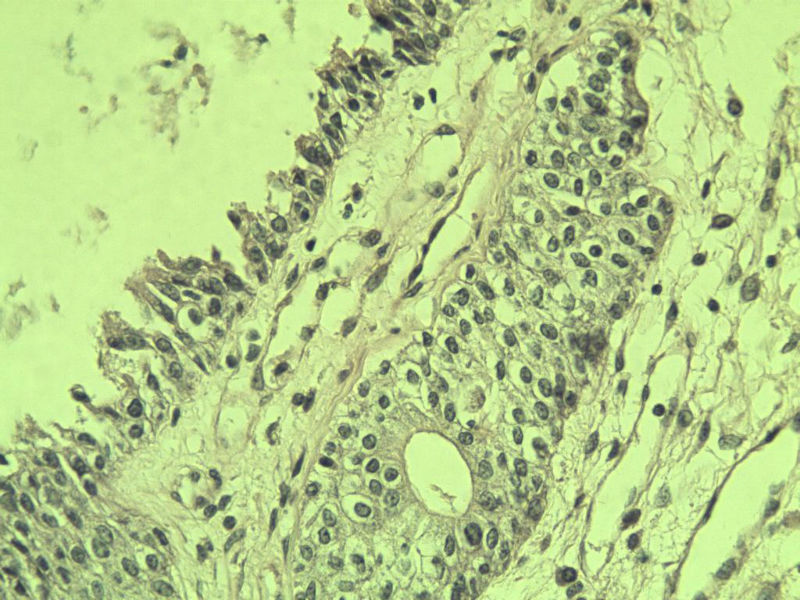

男 75岁 因排尿困难半年行前列腺切除术,体积 4 × 3 × 2.5 cm3,切面灰白,实性,质韧。请各位老师看看 有问题没? 谢谢了!

良性前列腺增生伴尿路上皮化生

前列腺增生症伴鳞化

前列腺增生伴尿路上皮鳞化及Brown巢形成,未见恶性。

良性前列腺增生伴brunnerr巢形成